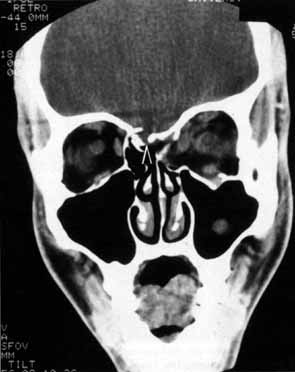

CASE 1 A 70-year-old woman presented with a 6-month history of progressive diplopia and ptosis. She demonstrated complete right third, fourth, and sixth cranial nerve palsies, and hypesthesia of cranial nerve V1 (Fig. 22A). The right pupil was dilated. Computed tomography (CT) disclosed an intracavernous aneurysm (see Fig. 22B). The so-called superior orbital fissure syndrome occurs when an infiltrative, inflammatory, or ischemic event occurs within the superior orbital fissure, but not in the orbital apex.4 A complete superior orbital fissure syndrome occurs when all the neurovascular components passing through the superior orbital fissure are damaged, producing a total ophthalmoplegia, ptosis, and anesthesia of cranial nerve V1 (see Fig. 22A). The pupil may be dilated, miotic, or midposition and fixed, depending on the balance of parasympathetic and sympathetic damage. The superior ophthalmic vein, best seen on CT, may be dilated if venous outflow from the orbit is obstructed. Clues to venous outflow obstruction are increased intraocular pressure, fullness of the upper eyelid, and hyperemia of the deep Tenon's vessels. Ophthalmoscopically, the retinal veins may be dilated. The effect of a lesion in the superior orbital fissure or the anterior cavernous sinus cannot be differentiated clinically (see Fig. 22B). When the posterior cavernous sinus becomes involved, hypesthesia of cranial nerve V2 may also be present. The only difference between a superior orbital fissure syndrome and an orbital apex syndrome is the presence of visual loss caused by optic nerve involvement. Visual acuity, color vision, or the visual field are abnormal. An ipsilateral relative afferent pupil defect is present. CASE 2 A 30-year-old man noted diplopia and right ptosis for the past month. The patient demonstrated normal vision and symmetric pupils but had a neurogenic ptosis (Fig. 23A) and limited right supraduction (Fig. 23B). Otherwise his extraocular movements were full. CT demonstrated an intracranial aneurysm of the posterior communicating artery aneurysm (Fig. 23C). Anatomically, the third cranial nerve branches into its superior and inferior divisions as it enters the orbit through the superior orbital fissure. Superior branch damage results in ptosis (levator muscle) and decreased supraduction (superior rectus muscle). Inferior branch damage results in decreased adduction (medial rectus), decreased infraduction (inferior rectus), decreased excycloduction (inferior oblique), and a dilated pupil (parasympathetic). Anatomically, a cranial nerve III branch nerve lesion seems to imply an anterior cavernous sinus or orbital apex localization. However, functionally, the third cranial nerve may bifurcate in the intracranial portion of the nerve, so cranial nerve III branch nerve palsies have been demonstrated with intracranial lesions. The localizing finding of a cranial nerve III branch nerve lesion is therefore not absolute (see Fig. 23).46 CASE 3 A 12-year-old child was referred by his school nurse because he had been complaining intermittently of double vision and the nurse had noted intermittent right ptosis. The child presented with a right ptosis and limited infraduction of the left eye (Fig. 24A). The ptosis worsened with prolonged up-gaze. A Cogan lid twitch was noted on the right with upward saccades. Injection of 1 mg of edrophonium resulted in complete resolution of diplopia and ptosis (Fig. 24B). The diagnosis was myasthenia gravis. Most orbital and cavernous sinus lesions produce afferent and efferent palsies in an anatomic pattern, for example, the superior orbital fissure has cranial nerves III, IV, VI and V1. When the pareses are not localized anatomically, or when there is variability in findings over time, one should include carcinomatosis or myasthenia gravis (see Fig. 24) in the differential diagnosis. Fatigability and a Cogan lid twitch strongly suggest myasthenia gravis. CASE 4 A 52-year-old woman presented with diplopia when looking to her right. She had noted a red right eye for the past 3 months (Fig. 25A). Visual acuity was 20/20 in both eyes and the pupils were normal. The right eye was limited in abduction. Forced duction testing showed abduction of the right eye to be restricted. Intraocular pressures were 23 mm Hg OD, and 15 mm HG OS. CT showed a dilated right superior ophthalmic vein (Fig. 25B) which was shown to be caused by a dural cavernous fistula. The right medial rectus muscle was also enlarged (Fig. 25C) because of blood engorgement, reducing muscle compliance, which accounted for the restricted abduction. Carotid cavernous fistulas can develop either as a result of trauma or spontaneously.47 A direct carotid cavernous fistula results from a tear in the intracavernous carotid artery with arteriolization of the cavernous sinus and superior orbital vein. Concomitant cranial nerve III, IV, VI, V1 and V2 paresis, elevated intraocular pressure, proptosis, and distention of the deep Tenon's vessels anteriorly (see Fig. 25A) with neuroradiologic evidence of an enlarged superior ophthalmic vein are common (see Fig. 25B). Ophthalmoplegia may also occur on a restrictive basis because of engorgement of the extraocular muscles with blood (see Fig. 25C).36 Dural carotid cavernous fistulas occur where small branches of the intracavernous carotid rupture, allowing access of arterial blood to the cavernous sinus. Typically, the findings are similar to a direct carotid cavernous fistula but of less magnitude. There is no history of trauma, and typically occurs in older persons. However, there is crossover between these two types of carotid cavernous fistula. An excessive ocular pulse tonographically may be helpful in the diagnosis of a carotid cavernous fistula in such cases.48 CASE 5 A 51-year-old woman was referred by her internist for left proptosis. The patient had noted diplopia for the past month but denied blurred vision or pain. Past history was significant for breast carcinoma requiring mastectomy. Vision was 20/20 in both eyes and the pupils were normal. Extraocular movements of the right eye were limited. Forced ductions were restricted. Exophthalmometry readings were 14 mm OD and 18 mm OS (Fig. 26A). CT disclosed a mass encircling the right globe (Fig. 26B). Biopsy disclosed metastatic scirrhous breast carcinoma retracting the right globe.